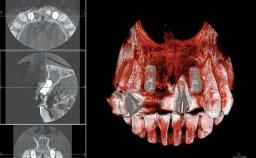

Replacement of Six Teeth with a Fixed Dental Prosthesis on Four Bone-Level Implants

In November 2010, a 44-year-old woman presented to the Harvard School of Dental Medicine seeking options to replace her failing six-unit conventional prosthesis. Having served for approximately 10 years, the fixed partial denture had repeatedly needed recementation after chronic dislodgement over the past few months. Following these episodes, the patient requested further evaluation of her current prosthesis and showed interest in exploring other options for a fixed solution. The patient was in good overall health, presenting with no systemic contraindications to implant therapy or any history of allergies; she did not smoke and was on no medications. Being a well-motivated individual, she regularly saw her general dental practitioner and effectively complied with oral hygiene requirements.